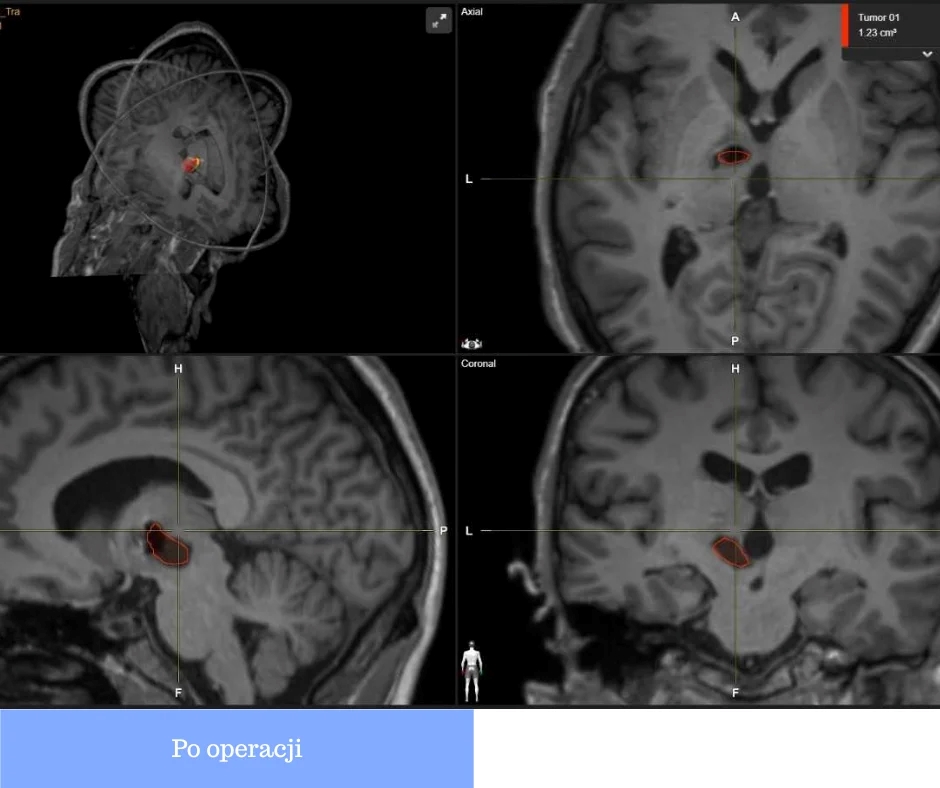

🔬 У рамках проєкту NeuroExcellence/Нейродосконалість без кордонів лікарню було оснащено високоточною системою нейронавігації. Це інноваційне обладнання дозволяє нейрохірургам працювати з максимальною точністю, мінімізуючи ризики для пацієнта, уникати складних та травматичних втручань і значно скорочувати період відновлення.

Саме нейронавігація стала вирішальним фактором під час надзвичайно складної операції, коли лікарі змогли провести мінімально інвазивне втручання замість небезпечної трепанації черепа. Завдяки точному доступу через голку всього 2 мм операція пройшла успішно.

👤 Коротко про пацієнта: 30-річний чоловік мав серйозні порушення мовлення, зору та координації через ураження в головному мозку. Уже після операції його стан різко покращився — він знову почав вільно говорити та повернувся до нормального життя.